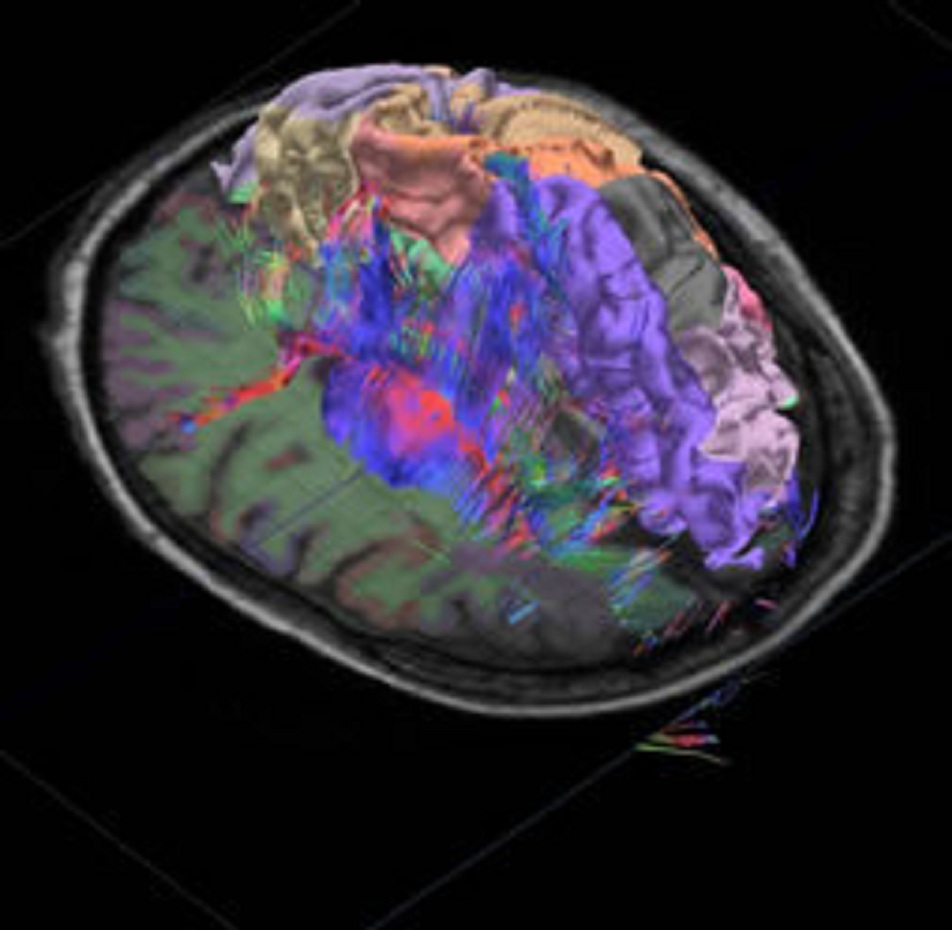

La barrera hematoencefálica impide el tratamiento de zonas cerebrales profundas o difícil acceso. La nanorrobótica podría llegar hasta ellas para liberar allí agentes terapéuticos. En la imagen: tracto de fibras nerviosas en 3D, segmentación cortical e imagen IRM del cerebro humano. Fuente: Allen Institute for Brain Research.

Por otra parte, ya sin componentes naturales, recientemente científicos de la Universidad de Montreal, en Canadá, han desarrollado unos “agentes nanorrobóticos” con una capacidad importante: pueden abrir la barrera hematoencefálica, que es la densa formación celular que protege al cerebro.

Tras atravesar dicha barrera, estos agentes minúsculos pueden liberar moléculas terapéuticas para el tratamiento localizado de tumores (en general, la barrera hematoencefálica impide que al cerebro lleguen el 98% de las moléculas terapéuticas).

Ese calor genera un estrés mecánico sobre la barrera hematoencefálica, lo que hace que esta se abra temporalmente (durante unas dos horas), ha informado la Universidad de Montreal a través de un comunicado difundido por AlphaGalileo. Esto es lo que permite una apertura temporal y localizada de la barrera para la difusión de agentes terapéuticos en el cerebro.

El avance es importante porque, en la actualidad, este punto solo puede conseguirse con cirugía. Pero a veces esta tampoco es suficiente, porque ciertos tipos de tumores se encuentran en el tronco cerebral, entre los nervios, lo que hace imposible alcanzarlos.

Por otra parte, ya sin componentes naturales, recientemente científicos de la Universidad de Montreal, en Canadá, han desarrollado unos “agentes nanorrobóticos” con una capacidad importante: pueden abrir la barrera hematoencefálica, que es la densa formación celular que protege al cerebro.

Tras atravesar dicha barrera, estos agentes minúsculos pueden liberar moléculas terapéuticas para el tratamiento localizado de tumores (en general, la barrera hematoencefálica impide que al cerebro lleguen el 98% de las moléculas terapéuticas).

Ese calor genera un estrés mecánico sobre la barrera hematoencefálica, lo que hace que esta se abra temporalmente (durante unas dos horas), ha informado la Universidad de Montreal a través de un comunicado difundido por AlphaGalileo. Esto es lo que permite una apertura temporal y localizada de la barrera para la difusión de agentes terapéuticos en el cerebro.

El avance es importante porque, en la actualidad, este punto solo puede conseguirse con cirugía. Pero a veces esta tampoco es suficiente, porque ciertos tipos de tumores se encuentran en el tronco cerebral, entre los nervios, lo que hace imposible alcanzarlos.